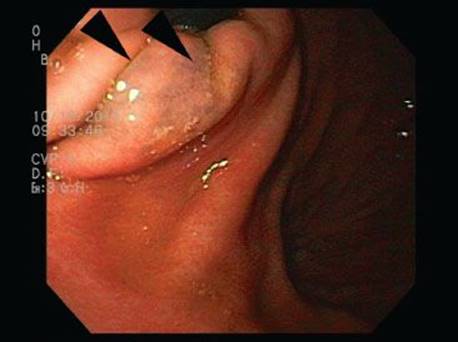

Gastric iron deposition is seen in up to 3.8% of upper tract biopsies (Fig. 2.228).23,24,183–185 In a study of 500 gastric biopsies, the deposition was demonstrated in three generalized patterns. Pattern A (also referred to as “nonspecific gastric siderosis”) was the most common subpattern and involved 2.2% of specimens (Figs. 2.229 and 2.230). This subpattern was associated with prior mucosal microhemorrhages, and the subtle depositions were predominantly identified within macrophages and stromal cells of the lamina propria. Pattern B (also referred to as “iron pill gastritis”) was seen in 0.8% of the biopsies and was consistently associated with ferrous sulfate therapy. This deposition was coarse and crystalline and predominantly identified in the extracellular and most superficial aspect of the biopsy (Figs. 2.231–2.234). In this subpattern, the background mucosa had a reactive gastritis/gastropathy pattern with erosions, ulcerations, and fibrino-inflammatory exudate common. In a separate study of 1,300 gastric biopsies, a similar “iron pill gastritis” injury pattern was detailed.184 This latter group reproduced the identical iron deposits in the laboratory by oxidizing ferrous sulfate tablets, providing clear evidence for the iron origin of these deposits. The mechanism of injury is a bit unclear in this subpattern. Some speculate that the iron pill has a direct caustic effect on the adjacent mucosa, whereas others suggest that the iron deposits may simply colonize previously injured mucosa. Pattern C (also referred to as “gastric glandular siderosis”) was the least common pattern, involving 0.6% of the specimens. This subpattern was associated with iron overload settings, such as hereditary hemochromatosis and multiple blood transfusions. The characteristic deposits were subtle, uniform, and identified in the deep antral and oxyntic glands (Figs. 2.235–2.239). The iron deposits can be highlighted blue with a Prussian blue iron special stain. Recognition is important to help prevent further injury and potential stricture formation (pattern B), to suggest pertinent iron overload evaluation (pattern C), and to avoid overdiagnosing the marked reactive epithelial change as dysplasia.

Figure 2.231 Iron pattern B/“iron pill gastritis”. In this dramatic case, coarse crystalline iron deposits are seen on the mucosa and within the luminal debris (arrowheads). A prominent reactive gastritis/gastropathy pattern is also seen in the background.